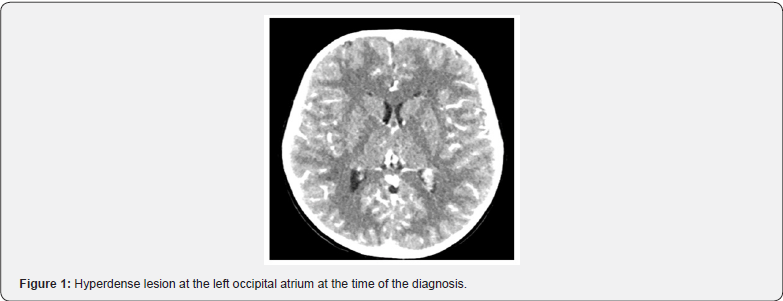

A 5 YO female had a 3-year history of episodic headache and vomiting 2 to 5 times per year for the last 3 years. The headaches subsided with emesis and were predominantly nocturnal according to the mother. Due to worsening of these manifestation, she was referred to our center for evaluation. Initially she was managed by the Neurological department considering it as a migraine because the patient did not have papilledema or any other finding in the neurological examination that could suggest intracranial hypertension. The first line of treatment was with sodium valproate for 6 weeks getting clinical improvement for a short time. For this reason, complementary studies were performed. In the CT we could observe a hyperdense image in the left occipital atrium which initially was thought to be a hemorrhage at that level (Figures 1-3). Due to the possibility of that image being a tumor, an MRI was performed in which the suspicion was cleared. At first hand we thought that the image we sought in the MRI was a choroid plexus papilloma, for that a surgical intervention was scheduled even thought there was no ventricular dilatation, but the clinical condition of the patient persisted. We performed an image guided posterior parietal craniotomy with ventricular access and total tumor resection.